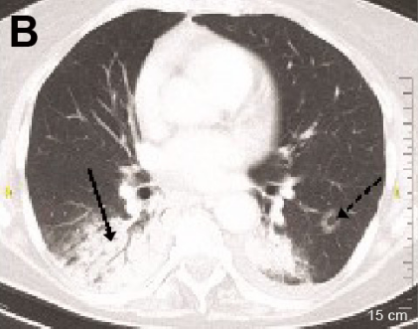

(1)急性间质性肺炎(AIP)/急性呼吸窘迫综合征(ARDS)/弥漫性肺泡损伤(DAD):弥漫性或多灶性磨玻璃影(GGO)或实变,并伴有肺容量减少和牵引性支气管扩张[17]

图片